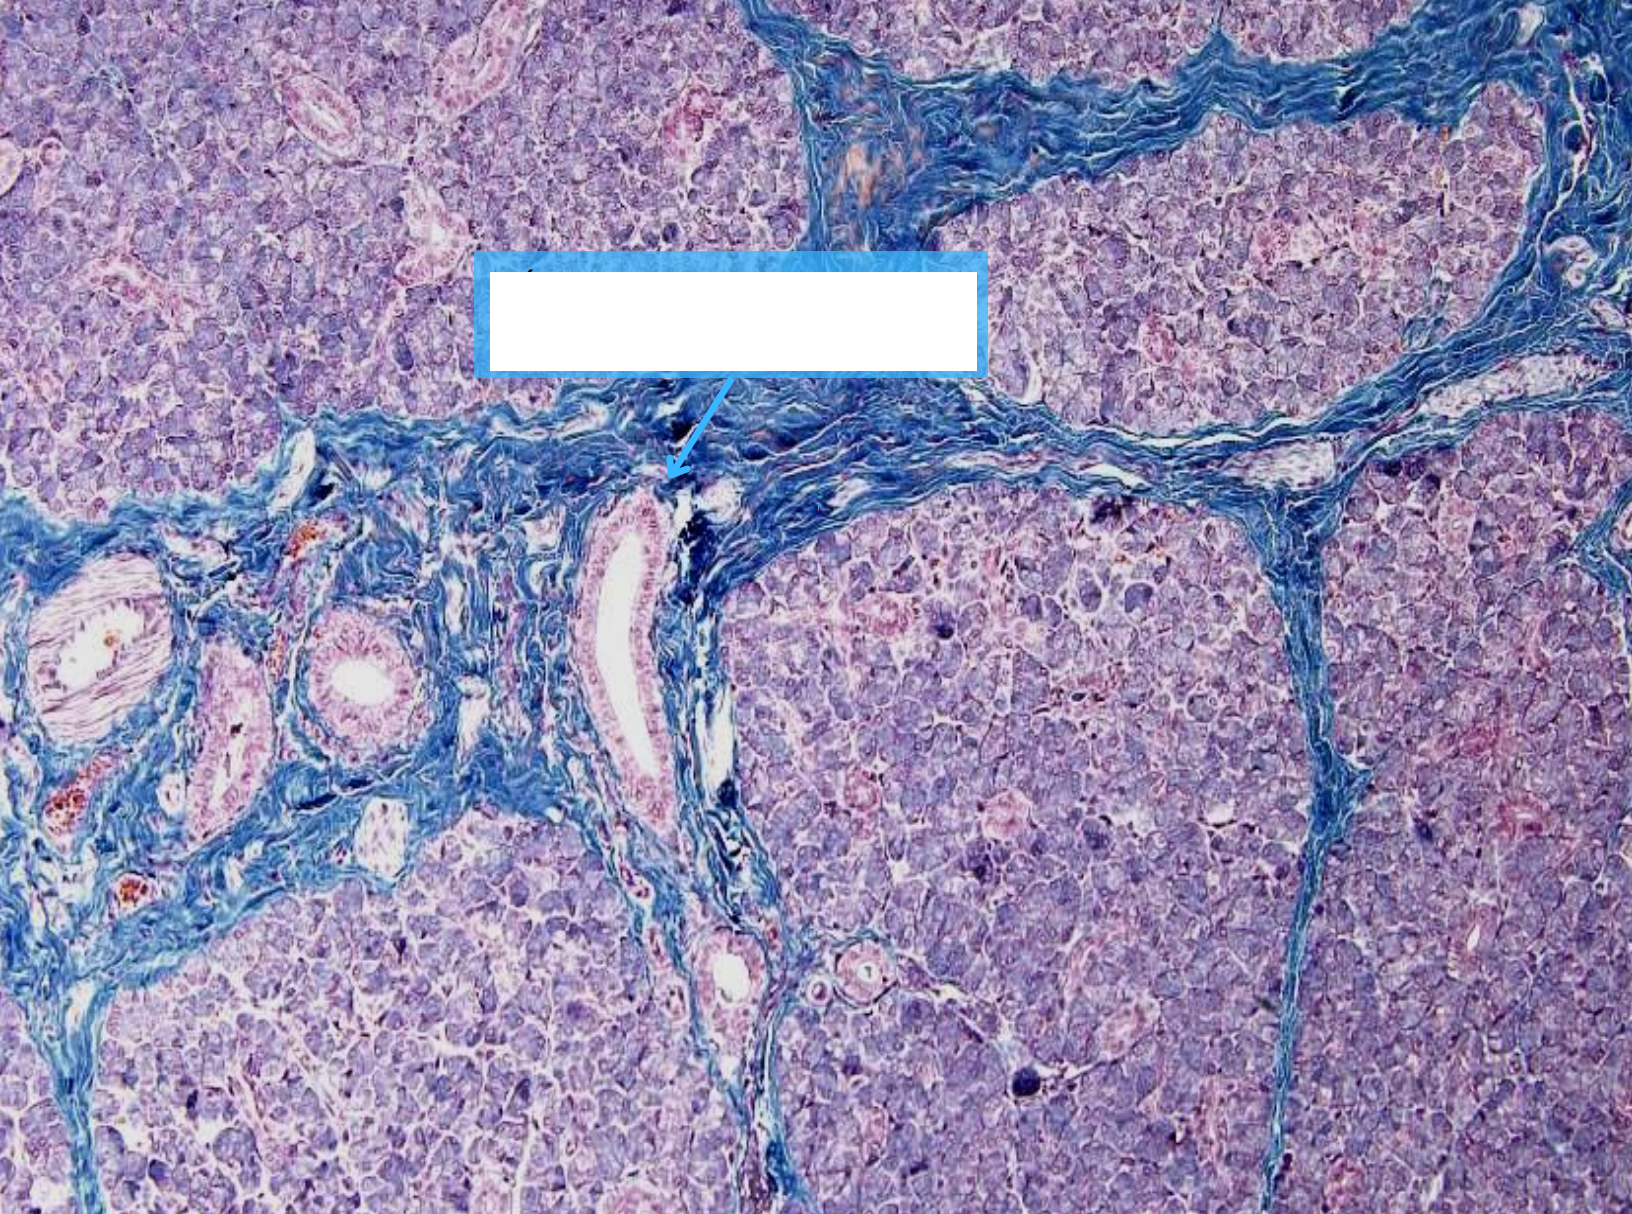

GAN:

Tĩnh mạch trung tâm tiểu thuỳ

Bè Remak (bè gan)

Mao mạch nan hoa

Tế bào Kupffer

Động mạch gan

Tĩnh mạch cửa

Ống mật